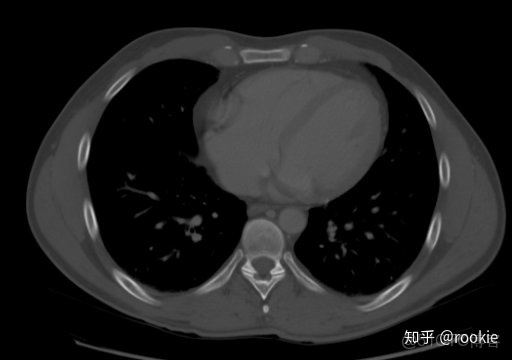

肺窗口窗口設置: (W:1600,L:-600)或(W:1500,L:-500)優點: 顧名思義,此窗口用於評估肺。靠近肺組織密度的高窗口水平(鑑於其低密度水平為低),並與寬窗口一起使用以提供良好的分辨率並可視化胸部的各種密度,例如肺實質以及相鄰的血管。

CLAHE算法增強局部對比度的X光圖像增強效果對比_#python 計算對比度_10

肺窗有助於評價肺,某些胸部病理學(如特定類型的結節)只能在這個窗口上看到。